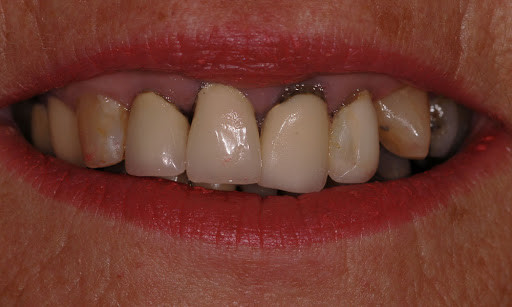

Identifying A Bruised Tooth

Most people don’t think of teeth when they think of bruises. Usually, it’s a black and blue knee versus a tooth. However, your teeth can become bruised, and it can be fairly painful. There are signs and symptoms you’ll need to be aware of, and you may need to visit the dentist depending on the severity. It may seem scary, but a bruised tooth is a common dental issue. And identifying a bruised tooth, is relatively straightforward.

A bruised tooth is often caused by an injury to the tooth. Similar to a bruise on your skin, a bruised tooth is a reaction to excess pressure or force. While your tooth won’t turn black and blue like your skin, it can become discolored and turn a gray tint.

A bruised tooth is painful and may ache because the soft tissue and ligaments around your tooth essentially absorb the impact of the trauma or injury. Just like a bruise on your skin, the capillaries around the injured tooth burst. The capillaries then travel to the opening of the tip of the root, which gives the tooth a pinkish discoloration.

The pinkish discoloration may turn gray, which can be permanent. A gray tooth may mean that the pulp inside your tooth is impacted, resulting in a higher risk of infection or decay. This can result in the need for a root canal Brentwood. If your tooth does not turn from pink to gray, you may be in the clear. However, you should see the best dentist Brentwood has, as they will want to monitor your tooth and help you in identifying a bruised tooth.